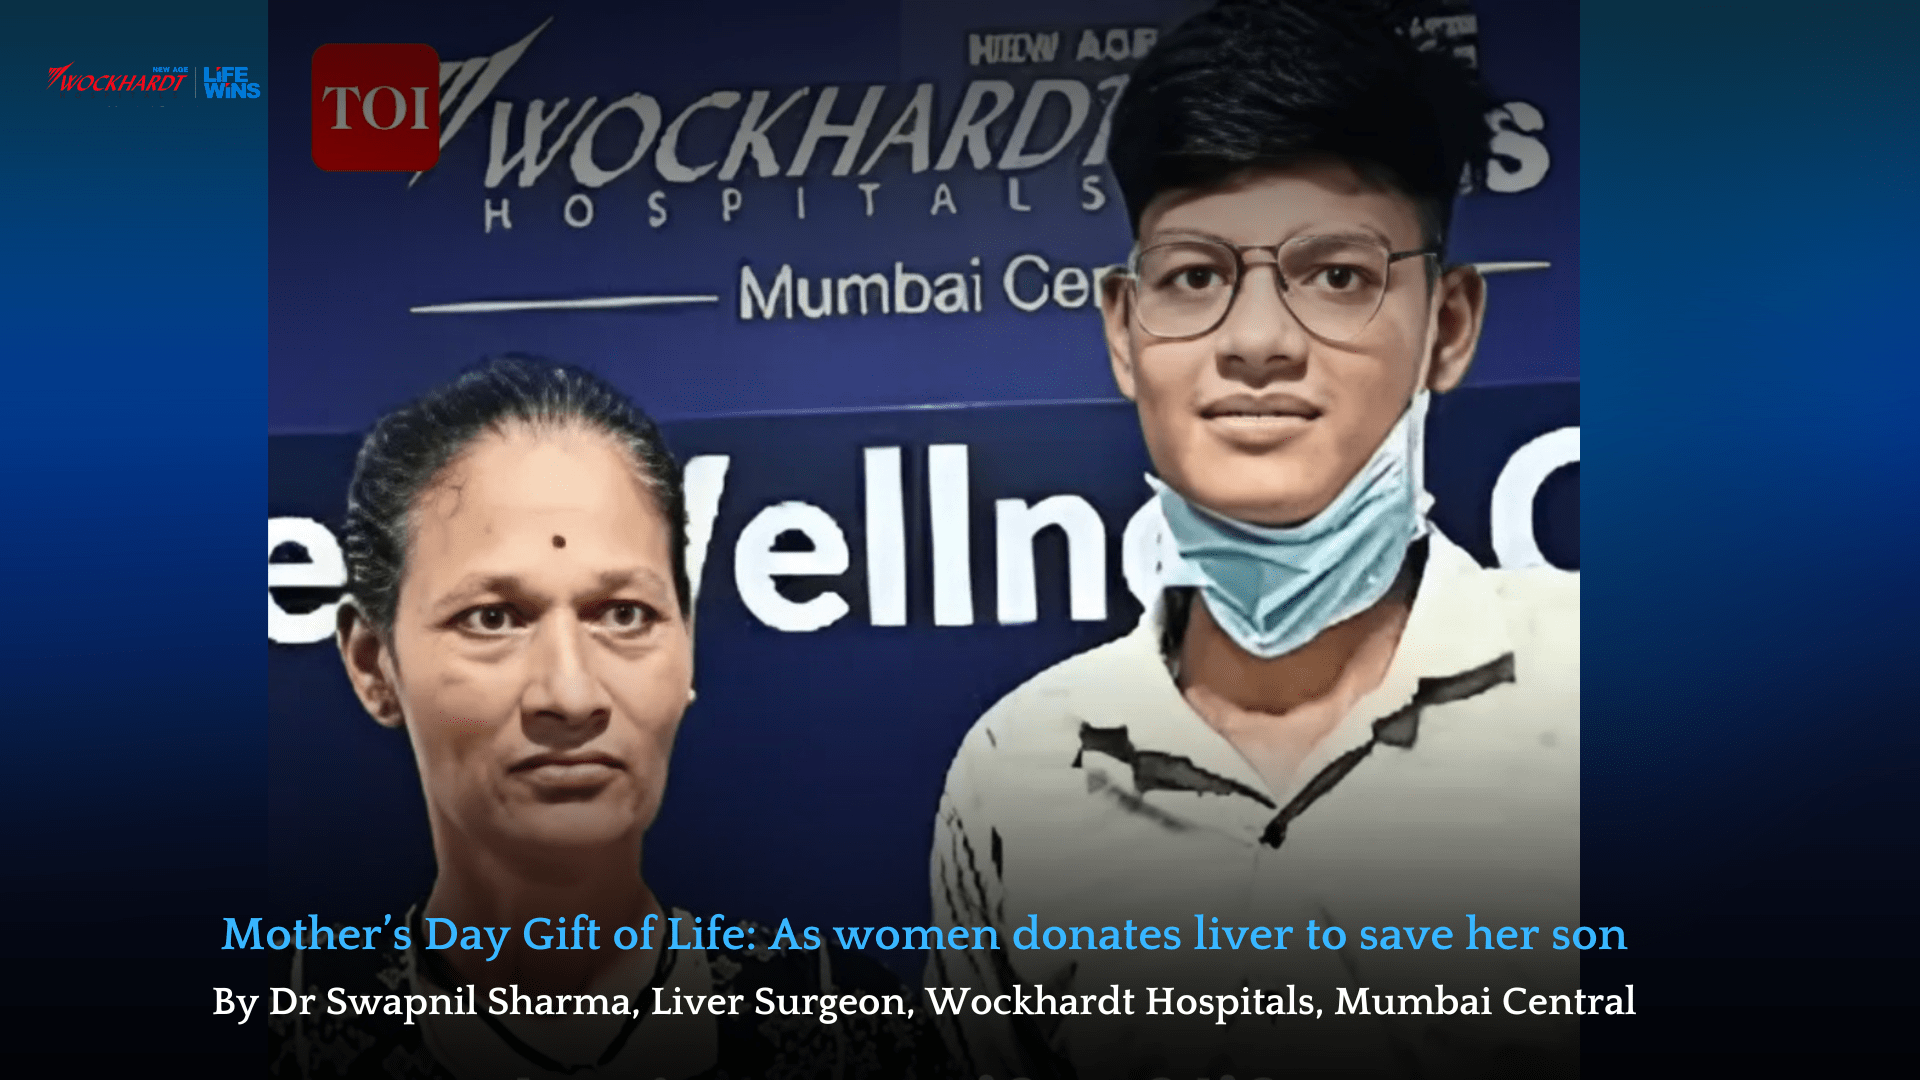

Mother Donates Liver to Save Son in Life-Saving Transplant by

Read More